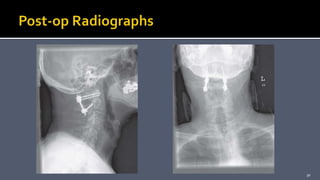

 Immobilize the patient in a halo-vest orthosis for 6 to 12

weeks after surgery.Then, flexion and extension radiographs

should be obtained to assess the fusion.

 If there is no motion, the halo can be removed.

 The patient should be followed clinically and radiographically

until fusion has occurred.

 Immobilize thepatient in a halo-vest orthosis for 6 to 12 weeks after surgery.Then, flexion and extension radiographs should be obtained to assess the fusion.  If there is no motion, the halo can be removed.  The patient should be followed clinically and radiographically until fusion has occurred. 45